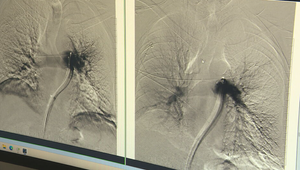

Sekundy rozhodujú. Lekári zachraňujú pacientov s pľúcnou embóliou unikátnym zákrokom Slovensko - aktuality